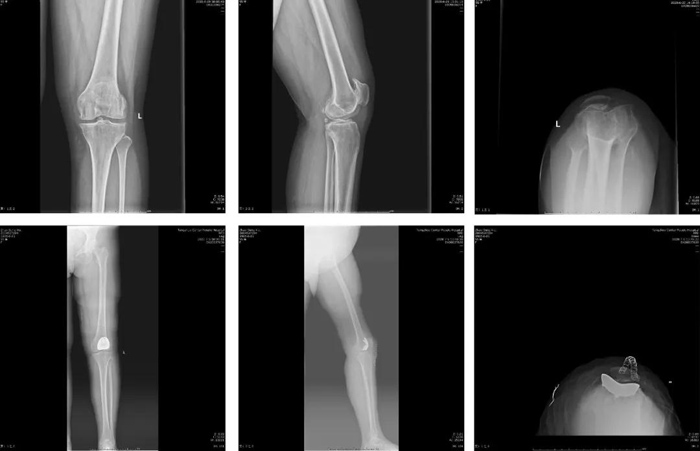

患者中年女性,55歲,因左膝關(guān)節(jié)疼痛7年,加重2年入院?;颊?/span>7年前無明顯誘因出現(xiàn)左膝關(guān)節(jié)疼痛,長距離行走或負(fù)重活動后疼痛加重,休息后可緩解。2年前左膝關(guān)節(jié)疼痛加重,下蹲、上下樓梯困難,嚴(yán)重影響日常生活。

7月9日,患者在全麻麻醉下行左側(cè)髕股關(guān)節(jié)置換術(shù)。手術(shù)時間約30分鐘,術(shù)后患者麻醉清醒后即下床活動,膝關(guān)節(jié)屈伸功能及疼痛情況較全膝關(guān)節(jié)置換術(shù)明顯改善,術(shù)后第3天出院。門診隨訪目前患者膝關(guān)節(jié)功能鍛煉良好,無并發(fā)癥出現(xiàn),患者滿意度高。